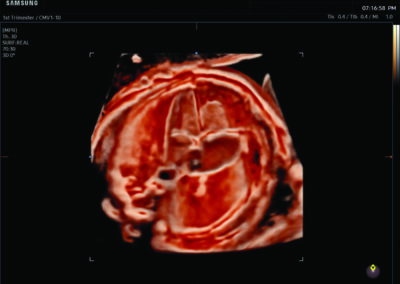

Procedural Services

Comprehensive, advanced and expert MFM care for high-risk pregnancies